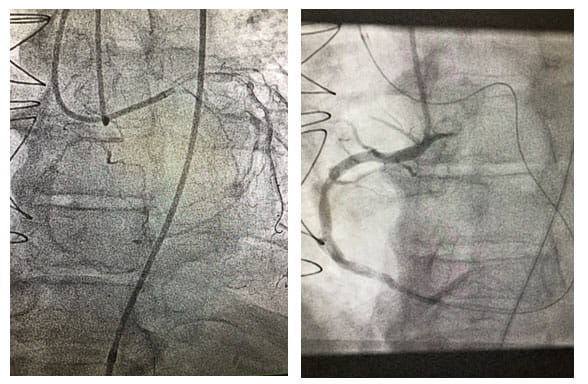

RCA Image around the plaqueProcedure going around the plaque in the RCA and stuck back in to open it up. 4 min crossing time, 65 min total procedure time. Patient’s symptoms of chest pain and SOB resolved after stent this artery.

Performing more than 60 CTO revascularizations per year, University Hospitals Harrington Heart & Vascular Institute is achieving a success rate well above the national average of 55 to 60 percent. Each case requires individual evaluation and precision technique. Often, the heart develops collateral arteries to compensate for the blockage, essentially creating its own bypass. "Sometimes, we actually have to go backwards through these collateral arteries to make a connection and place a stent to open the blockage," Dr. Poommipanit says.